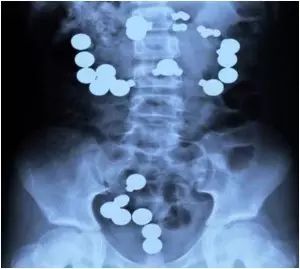

4.8岁的小女孩吞了一些东西。大家都以为是糖果之类的,看了X光之后才发现:这!是!磁!铁!

8岁的小女孩吞了一些东西。大家都以为是糖果之类的,看了X光之后才发现:这!是!磁!铁!